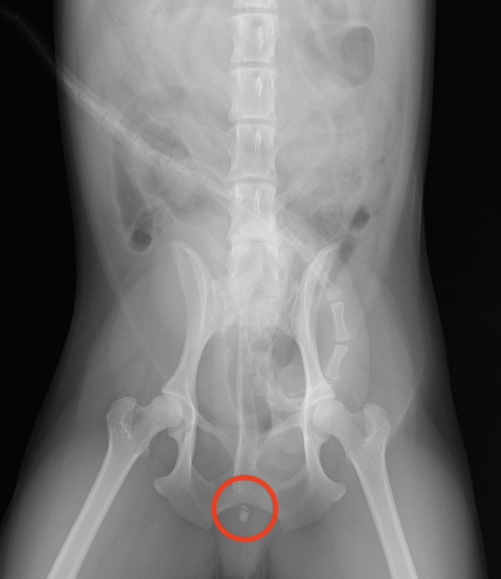

そこでレントゲン検査、腹部超音波検査を実施したところ膀胱内と尿道に結石を疑うような像が認められました。

レントゲン画像